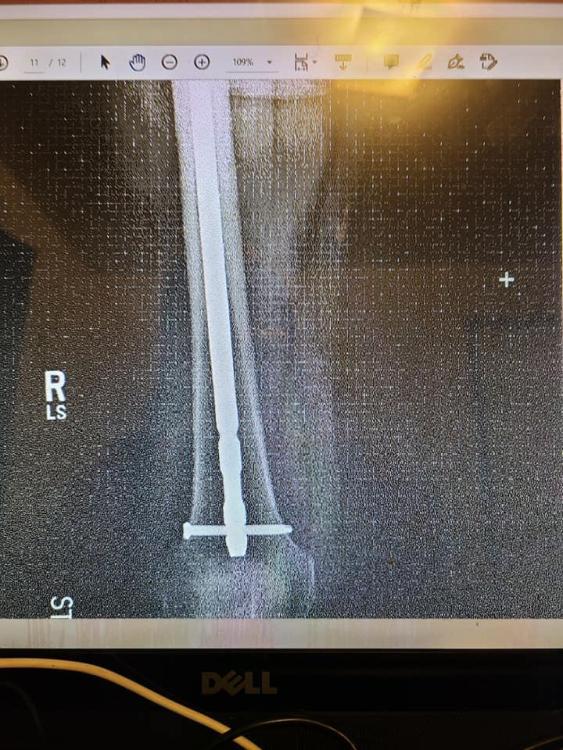

I know what you mean.    In August of 2020,  I slipped while bringing my dog back into my apartment.  I did the splits and shattered my greater trochanter in my right leg. Let's just say that I'm filled with titanium, nails and screws in my right leg.    I'm still not 100% but I can walk now.     It was a rough few months.

121736692_3566939370024380_4410654280752113959_n.jpg